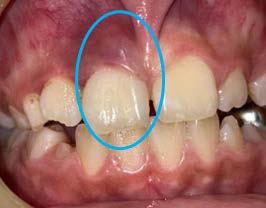

Las lesiones traumáticas de los dientes permanentes son comunes y afectan entre el 10.5% y el 17.3%. La extrusión, la luxación lateral y la intrusión se encuentran entre los tipos más graves de traumatismo dental que pueden alterar el suministro vascular a la pulpa. Radiográficamente, las partes apical y lateral del alvéolo parecen vacías y, en general, el espacio del ligamento periodontal está agrandado. La obliteración del canal pulpar (OCP) y la necrosis pulpar (NP) son las consecuencias más frecuentes de la luxación extrusiva, mientras que la reabsorción radicular (RR) es menos frecuente. Las complicaciones dependen de factores como la gravedad de la lesión, el estadio de desarrollo radicular y la presencia de una alta carga bacteriana bucal. Las complicaciones pulpares y periodontales son más frecuentes en dientes con raíces completamente formadas que en ápice abierto. La prevalencia de obliteración del canal pulpar (OCP) como consecuencia de lesiones por avulsión y luxación está entre el 3 y el 24%. Por el contrario, es muy poco probable que los dientes con ápice cerrado presenten revascularización y a menudo desarrollan

Figura 2. Imagen representativa de una luxación extrusiva en el órgano dental 11 que presenta un cambio de coloración en la encía.

necrosis pulpar. Las lesiones por luxación extrusiva requieren un tratamiento inmediato, consistente en reposicionamiento y estabilización. El tratamiento comienza con un correcto diagnóstico clínico y radiográfico, seguido del reposicionamiento manual del diente en el alvéolo y la colocación de una férula flexible, para permanecer in situ durante aproximadamente 2 semanas.6

Entre todas las lesiones orofaciales, las lesiones dentales traumáticas (TDI) son una de las más prevalentes. Representa el 18% de todas las lesiones en niños de 0 a 6 años (Figura 2) y Las lesiones por luxación se pueden clasificar en varios tipos según el grado de desplazamiento: conmoción cerebral, subluxación, luxación lateral, extrusión y avulsión. La raíz del germen del diente temporal y del permanente se encuentran muy cerca, por lo que las complicaciones a largo plazo de las TDL, como la infección de los dientes temporales, también pueden dañar los dientes sucesores en desarrollo. La prevalencia de lesiones por luxación es alta entre los niños pequeños debido a la naturaleza resistente de su hueso alveolar y sus estructuras de soporte (Figura 3). Se ha informado que las lesiones por intrusión causan más alteraciones de la mineralización en